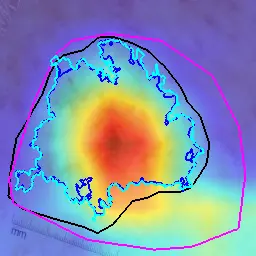

What Can We Learn from Inter-Annotator Variability in Skin Lesion Segmentation?

Kumar Abhishek, Jeremy Kawahara, Ghassan Hamarneh

Medical Image Computing and Computer-Assisted Intervention (MICCAI) ISIC Skin Image Analysis Workshop (MICCAI ISIC), 2025

(Best Paper Award | SFU FAS 3MT Runner-Up | SFU 3MT Finalist | Invited 3MT at University Women's Club of Vancouver)

We show a statistically significant association between inter-annotator agreement (IAA) and the malignancy of skin lesions, and leverage this association to improve lesion diagnosis performance. [Abstract] [BibTeX] [Presentation Slides]

Medical image segmentation exhibits intra- and inter-annotator variability due to ambiguous object boundaries, annotator preferences, expertise, and tools, among other factors. Lesions with ambiguous boundaries, e.g., spiculated or infiltrative nodules, or irregular borders per the ABCD rule, are particularly prone to disagreement and are often associated with malignancy. In this work, we curate IMA++, the largest multi-annotator skin lesion segmentation dataset, on which we conduct an in-depth study of variability due to annotator, malignancy, tool, and skill factors. We find a statistically significant (p < 0.001) association between inter-annotator agreement (IAA), measured using Dice, and the malignancy of skin lesions. We further show that IAA can be accurately predicted directly from dermoscopic images, achieving a mean absolute error of 0.108. Finally, we leverage this association by utilizing IAA as a “soft” clinical feature within a multi-task learning objective, yielding a 4.2% improvement in balanced accuracy averaged across multiple model architectures and across IMA++ and four public dermoscopic datasets. The code is available on GitHub.